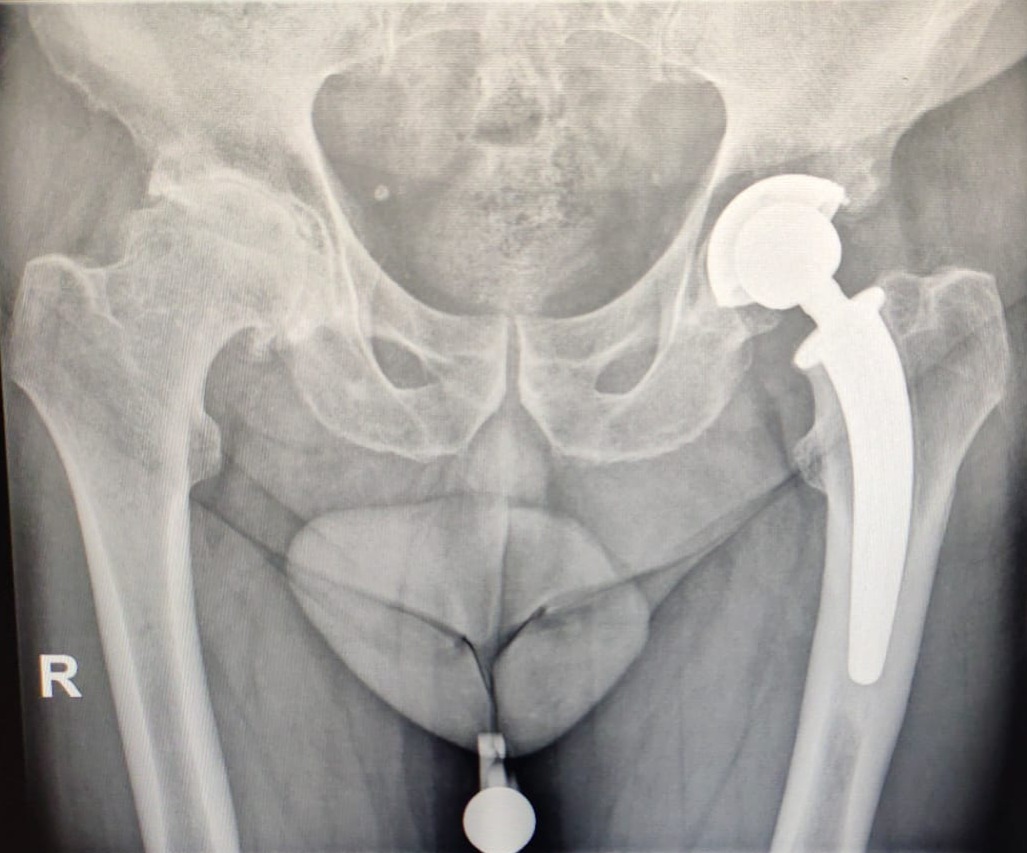

Radiografia Protesi Totale Anca Dott. Bonioli

Chirurgia dell'Anca

Dimentica i lunghi ricoveri del passato. Grazie alla Chirurgia a Risparmio Tissutale, curiamo l'artrosi dell'anca unendo la massima precisione chirurgica a un approccio mininvasivo preservando i muscoli glutei.